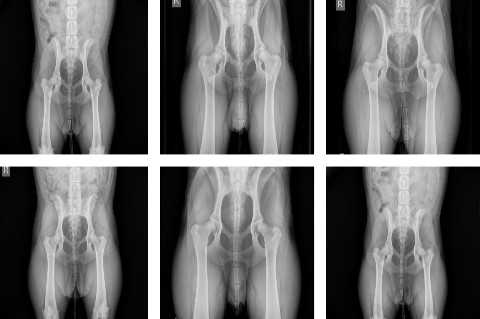

Ist eine bestehende Lahmheit lokalisiert, kann eine Röntgenuntersuchung sinnvoll sein, um das Ausmaß des Schadens zu ermitteln und die richtige Therapie einzuleiten. Frakturen, Luxationen und Bandabrisse sollten chirurgisch versorgt werden. Zerrungen und Prellungen benötigen meist nur Ruhe. Bei tumorverdächtigen Prozessen entscheidet das Biopsie-Ergebnis über das weitere Vorgehen.